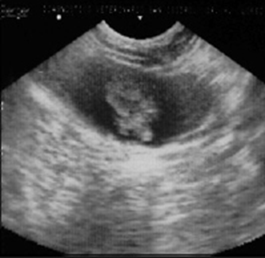

The patient, a 9-year-old female Great Dane canine, presents with intermittent clinical signs of cystitis. Urine culture confirms its bacterial origin. The established antibiotic therapy is ineffective. The diagnosis is reconsidered. The ultrasound report indicates the presence of two closely spaced hyperechoic images, one measuring 1.61 cm x 1.16 cm and the other measuring 1.40 cm x 1.08 cm, implanted in the dorsal wall of the fundus of the urinary bladder. They involve 1/3 of its thickness (Figure 19). A laparotomy and cystotomy are performed, and the tumor is exposed through the ventral surface of the bladder using the "glove finger" maneuver.

Figure 19 Ultrasonographic Image: 2 closely spaced, hyperechoic masses in the bladder measuring 1.61 cm x 1.16 cm and 1.40 cm x 1.08 cm.